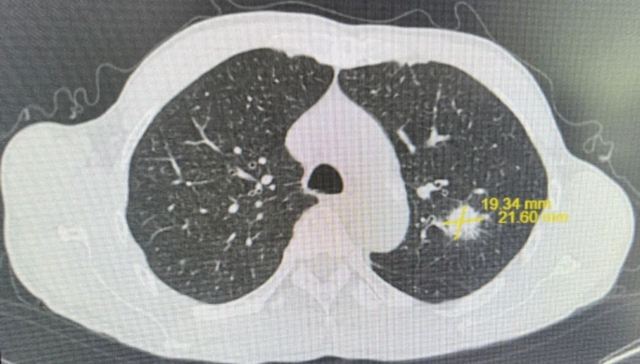

肺部CT:左肺上叶尖后段软组织结节,大小约2.1×1.9cm²,边缘见毛刺,结合病史,考虑肺转移可能。

综合检查结果,西医诊断为:鼻咽部恶性肿瘤(分化型非角化性癌)侵及口咽、咽旁间隙伴咽后、颈部转移淋巴结;肺继发恶性肿瘤;中医诊断为鼻咽癌(痰瘀互结)。